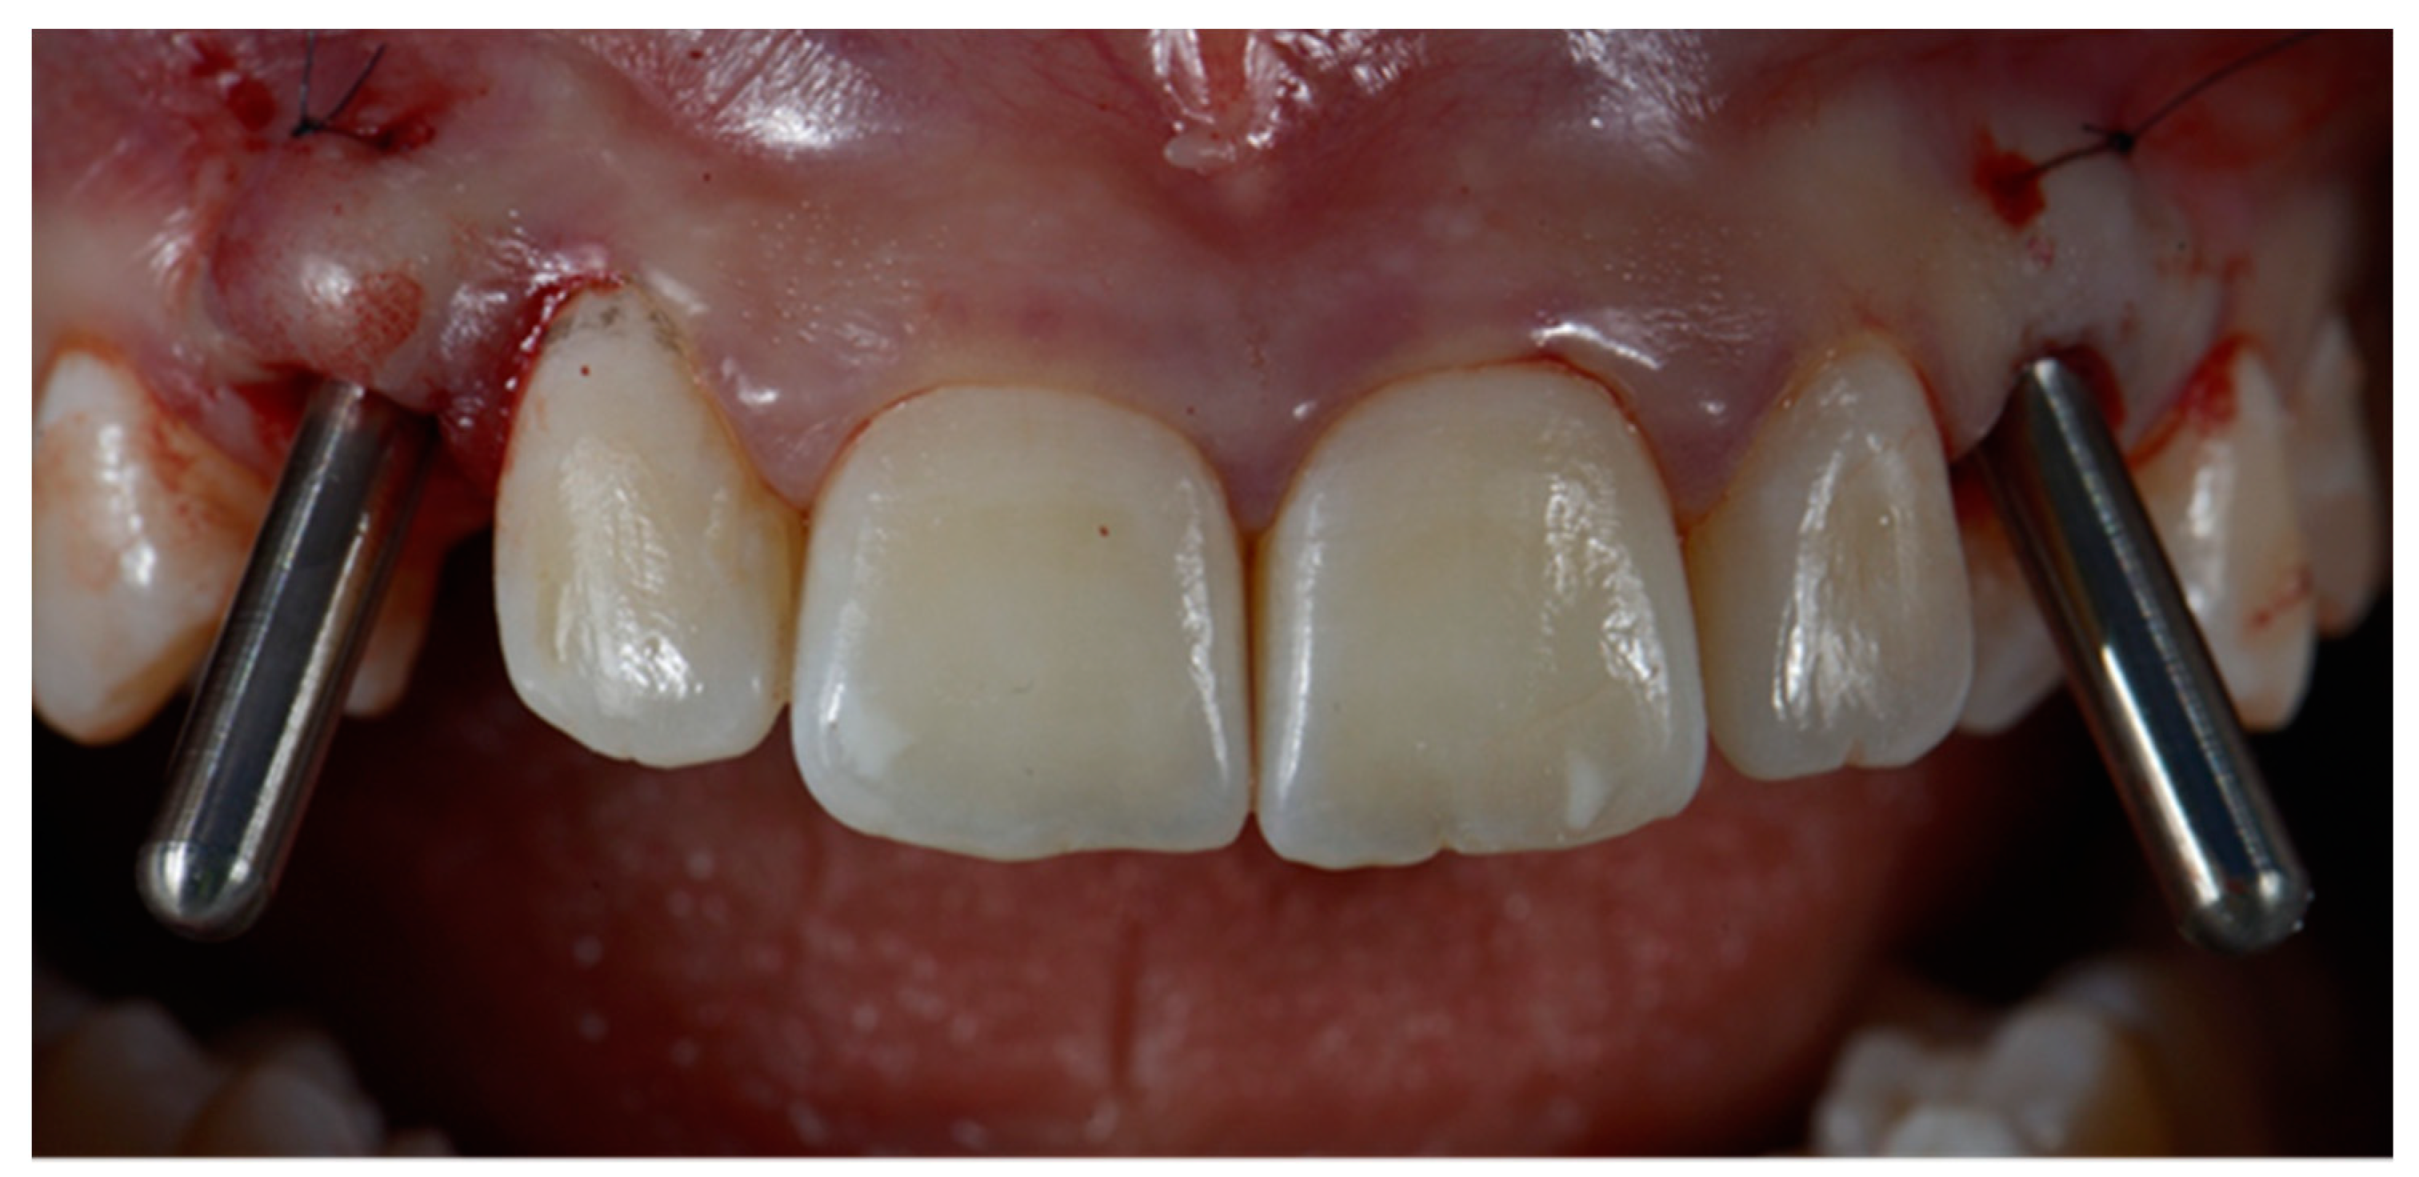

2.3. Surgical and Prosthetic Workflow

2.4. Outcome